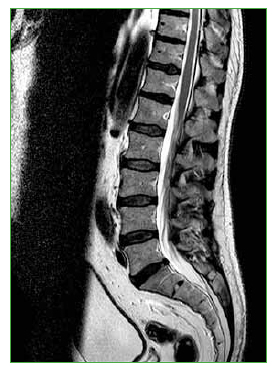

Las hernias discales intraesponjosas vertebrales o nódulos de Schmörl consisten en una herniación o una extrusión del núcleo pulposo del disco intervertebral a través del platillo vertebral hacia el cuerpo adyacente. Suelen asociarse a deformidades vertebrales, como la enfermedad de Scheuermann, o a enfermedades reumáticas, como la espondilitis anquilopoyética. En general, son hallazgos casuales y cuadros asintomáticos; son pocos los casos publicados de nódulos sintomáticos. Su aparición estaría relacionada con un platillo vertebral debilitado por traumatismo o estrés repetido. Cuando el nódulo es agudo o reciente, puede ser difícil diferenciar la degeneración benigna de una infiltración maligna o una infección. Presentamos un caso inusual de un nódulo de Schmörl doloroso en un hombre sin antecedentes de relevancia, que enmascaró una lesión metastásica de carcinoma pancreático a nivel lumbar. Se realiza una revisión bibliográfica. ABSTRACTIntraosseous disc herniation –or Schmörl nodes (SN)– are a herniation or prolapse of the nucleus pulposus of the intervertebral disc through the vertebral plate and into the adjacent vertebral body. They are usually associated with vertebral deformities, suchas Scheuermann’s disease, or rheumatic diseases, such as ankylopoietic spondylitis. In general, they are spontaneous and asymptomatic findings, and there are only a few reported cases of symptomatic nodes. The etiology is supposedly related to a weakened spinal plate due to trauma or repeated stress. When the node is acute or recent, it can be difficult to differentiate a benign degeneration from a malignant infiltration or infection. In this paper, we discuss the unusual case of a painful Schmörl node in a man with no relevant history and a masked metastatic lumbar spinal tumor originated from pancreatic cancer. We performed a literature review.Descargas